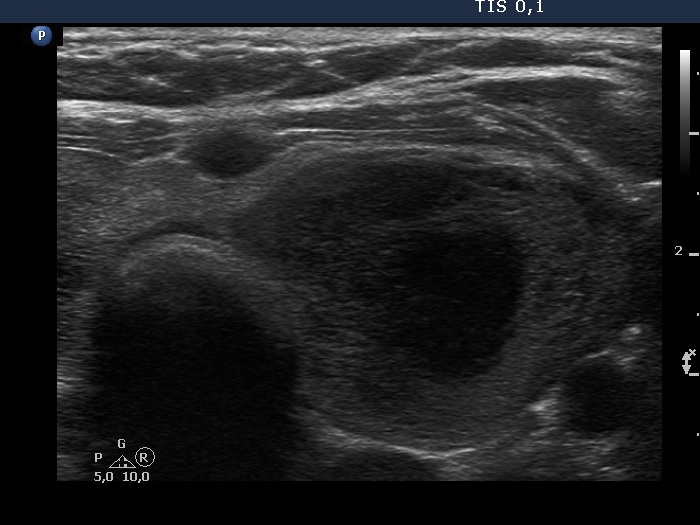

First examination (first, third and fifth rows of images):

Ultrasonography. The thyroid was echonormal and contained multiple inhomogeneous, partly blurred hypoechogenic and moderately hypoechogenic discrete lesions. Multiple lymph nodes were found on both sides of the neck.

Cytology was performed from 3 different thyroid lesions and resulted in a pattern corresponding to non Hodgkin lymphoma.